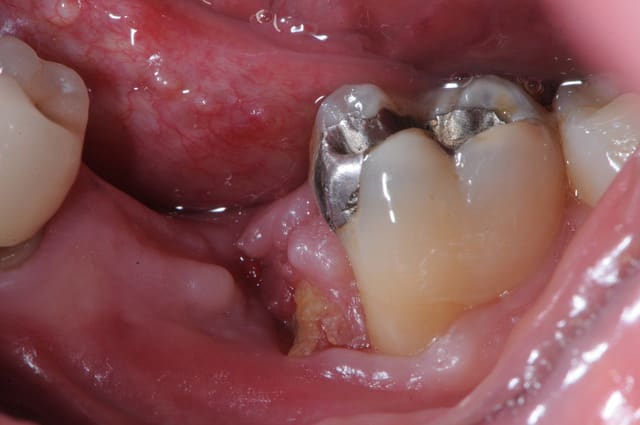

patient qui consulte lundi dernier pour avis implantaire pour 46

je regarde et je vois un petit morceau osseux bien vilain qui dépasse.

l'extraction a eu lieu il y a 4 mois par un confrère qui bosse bien et donc je ne remet pas en cause ses compétences.

l'extraction s'est pourtant bien déroulée et d'après le patient, les suites aussi. là j'en doute un peu plus mais bon...